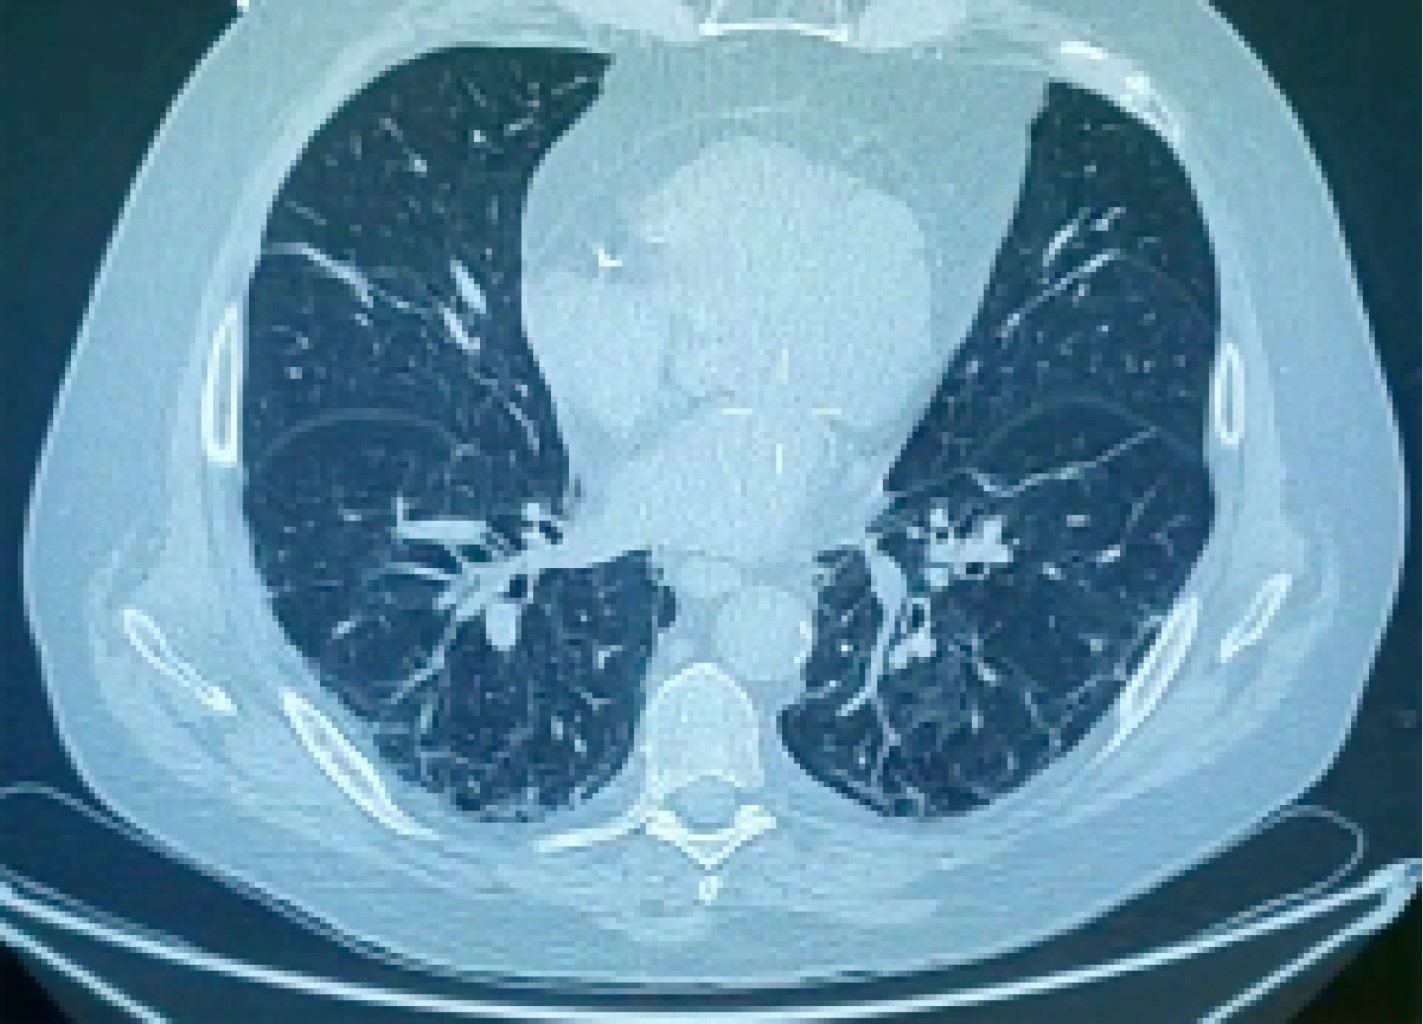

Figure 1

Figure 2

Figure 3